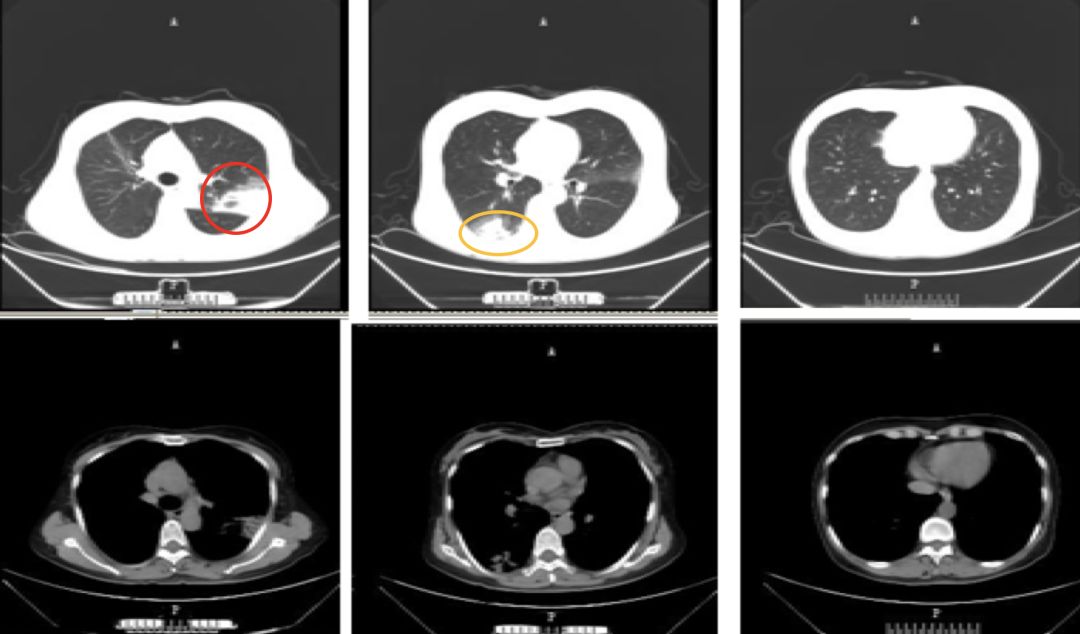

(呼吸与危重症医学科)经过临床、影像与病理综合分析,该患者最终诊断为亚急性纤维素性机化性肺炎。AFOP是2013年由美国胸科协会与欧洲呼吸协会发布的特发性间质性肺疾病的一个类型,发病年龄通常在50-70岁,男性发病率略高于女性,可分为特发性和继发性,临床表现可出现全身性及呼吸系统症状,病人可出现发热、胸闷、呼吸困难、咯血等。该病临床类型分为急性爆发型和亚急性2种类型,急性爆发型病情进展迅速,病人很快进展至ARDS,平均死亡时间为29天,死亡率高达90%。亚急性型病程大于2个月,该病人临床特点符合亚急性,亚急性预后较好,影像学表现可表现为多发斑片影、渗出影,结节影、可出现游走性,类似于COP影像学特点,但最终要有赖于病理诊断。AFOP病理学特征为肺泡腔出现纤维素沉积,无肉芽肿形成,无透明膜形成,无嗜酸粒细胞浸润,这一点需要与COP鉴别。OP的病理学特征为肺泡腔内可见肉芽肿形成,即肌纤维细胞和成纤维细胞,该点要与AFOP进行鉴别。

(呼吸与危重症医学科)该病人诊断亚急性AFOP明确,针对AFOP的治疗,国内外现有的指南以及资料暂无统一治疗标准,但目前公认糖皮质激素是AFOP的主要治疗药物,不论是特发性还是继发性因素引起的。特发性AFOP治疗需根据病情严重程度来选择治疗药物。目前治疗AFOP主要有三大类药物:第一类是糖皮质激素,第二类是免疫*制剂抑**,第三类是免疫球蛋白,以及支持治疗包括机械通气及ECMO。急性爆发性AFOP,病人病情重,短期内发展为呼吸衰竭,死亡率高,这种情况可选择激素冲击治疗,最大量可不超过1000mg/d,治疗时间长短及减量方案需要结合病人对药物的反应,病人年龄及恢复情况来综合判断。另外需要注意糖皮质激素的副作用,比如继发感染的问题、骨质疏松以及胃肠道粘急性病变以及肌病的问题。亚急性AFOP激素的选择也需要结合病人年龄、基础疾病的情况以及肺部病变严重程度来个体化定制治疗方案。激素需要静脉和口服序贯治疗,根据病人恢复情况规律减量。另外,继发性AFOP不要忽视原发病的治疗。

王静教授点评

该患者病情一波三折,该患者诊断亚急性AFOP明确,而且使用糖皮质激素后病灶明显吸收,病程转归是令人欣慰的。但我们在治疗过程中也有需要进一步完善的地方,比如说BALF要送细胞学分类,BALF对疾病的预测价值我们临床大夫要提高重视,同时要加强对病人的追踪随访。另外,多学科协作对病情诊断和治疗上都有很大指导意义。作为一名临床医生,不但要注重病人病史、临床表现、体格检查、实验室检查,还要对治疗经过做一个完整的梳理,病情诊断需要临床病理相结合,比如COP、SOP、AFOP有时从临床表现上难以区分,这时就需要我们从病理上进一步甄别。